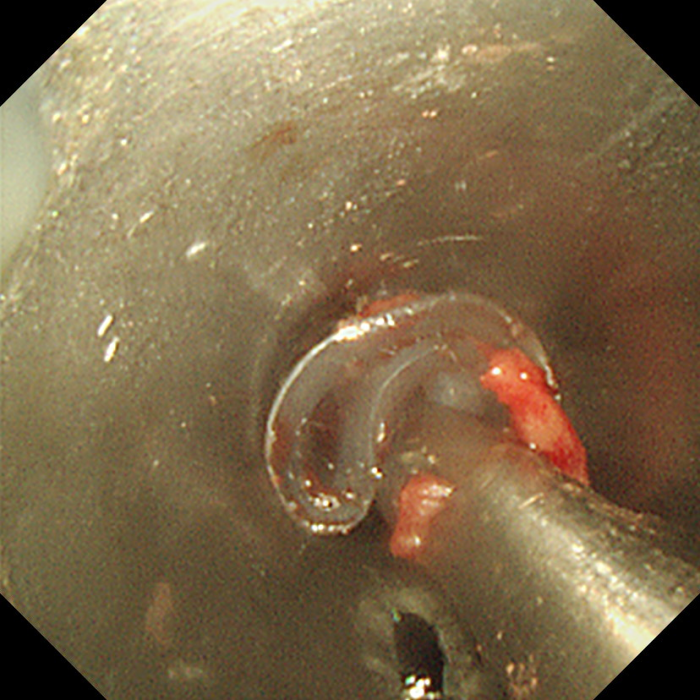

随后,肖奎博士带领团队开始手术。团队先行通过可弯曲支气管镜检查,发现声门下及气管上端有瘢痕组织增生及少许坏死物附着,气管瘢痕扭曲而狭窄,原置入的硅酮支架已向气管远端移位。在支气管镜引导下,肖奎博士顺利将硬质支气管镜插入气管,扩张了狭窄段,并对增生的肉芽组织进行了旋切治疗。最后,在狭小且易出血的气道内,肖奎博士通过硬质支气管镜,使用硬镜钳精准而顺利地将移位的硅酮支架完整取出。